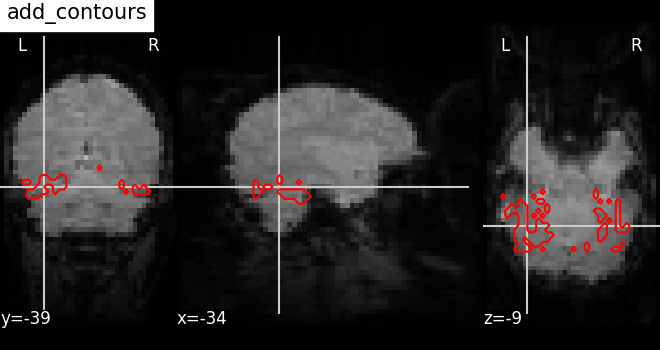

7.4. Adding overlays, edges, contours, contour fillings, markers, scale bar¶

To add overlays, contours, or edges, use the return value of the plotting

functions. Indeed, these return a display object, such as the

nilearn.plotting.displays.OrthoSlicer. This object represents the

plot, and has methods to add overlays, contours or edge maps:

display = plotting.plot_epi(...)